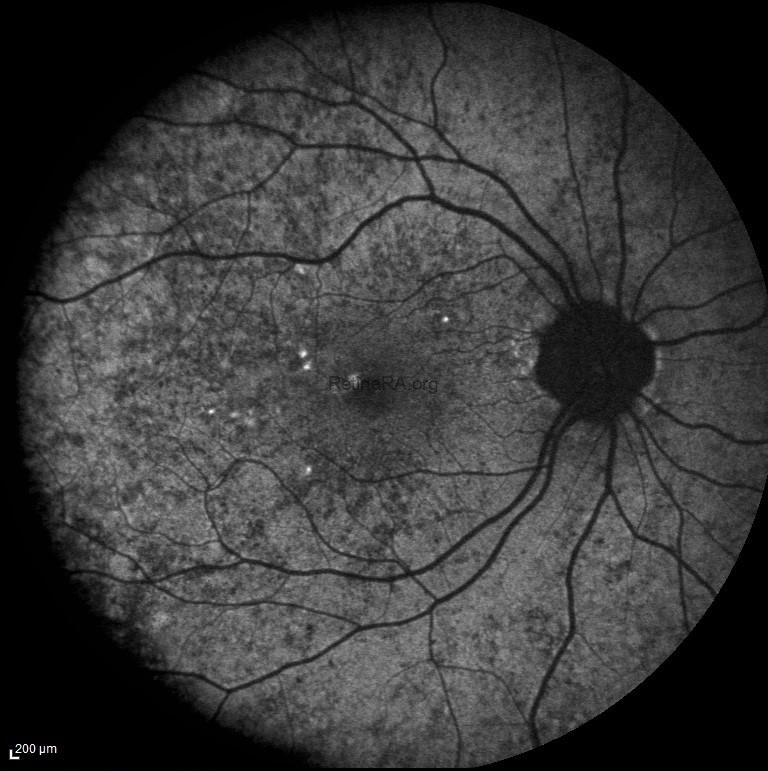

In this patient’s fundus autofluorescence (FAF) imaging demonstrates a characteristic mottled pattern of autofluorescence, reflecting the underlying mosaicism of RPE health due to X-chromosome inactivation. Areas of normal or relatively preserved RPE exhibit normal autofluorescence, while regions of RPE dysfunction or atrophy appears as zones of hypoautofluorescence.